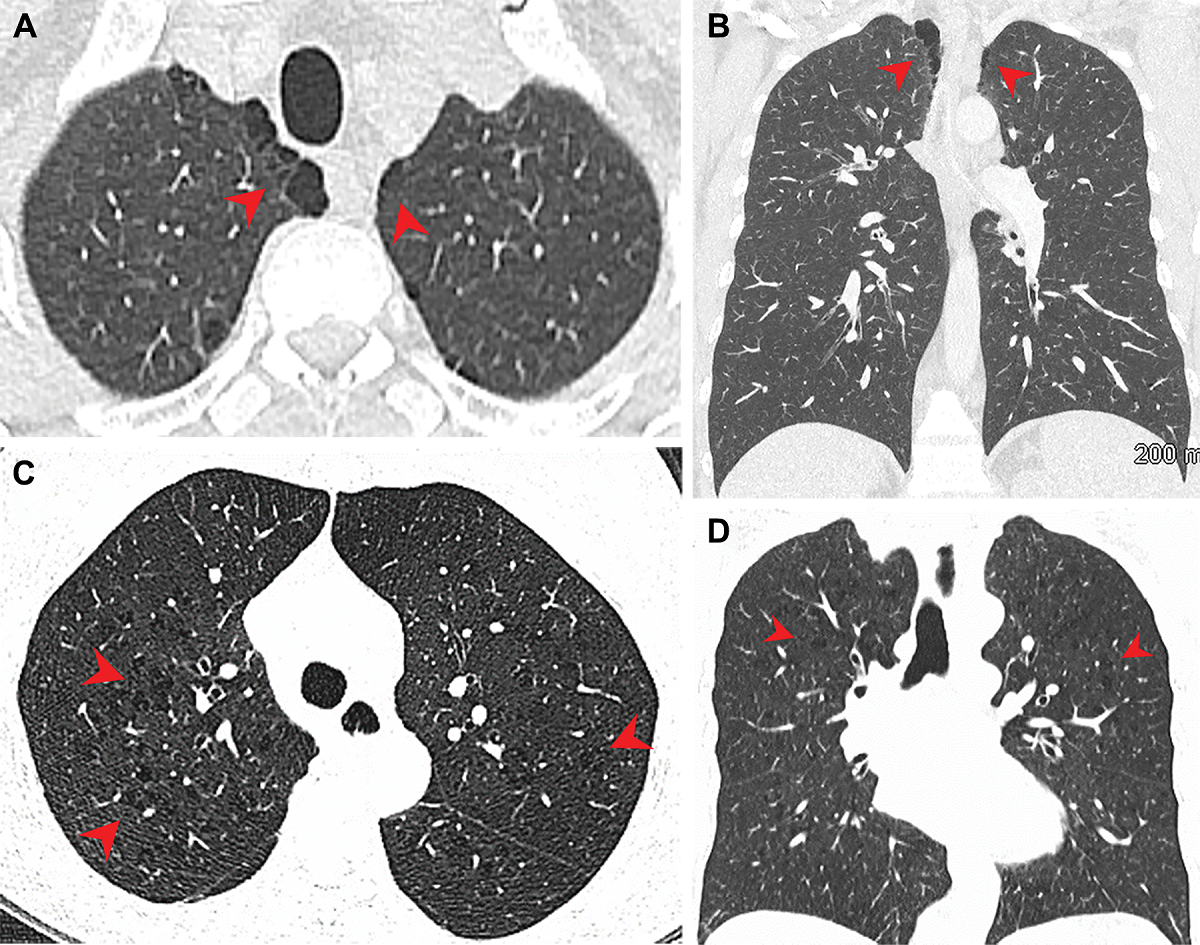

Quatre scans montrant les poumons de fumeurs de marijuana et de cigarettes.

Pulmonary emphysema in (A, B) marijuana, (C, D) tobacco smokers. (A) Axial + (B) coronal CT images in male (44) marijuana smoker show paraseptal emphysema in bilateral upper lobes. (C) Axial + (D) coronal CT images in female (66) tobacco smoker...